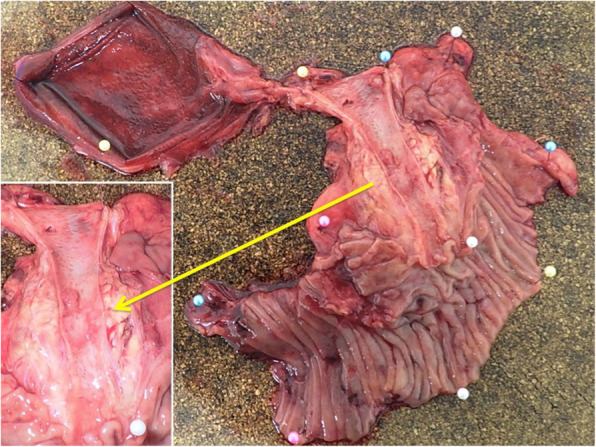

Under a diagnosis of primary cholangiocarcinoma (CCA) of the DBD, a subtotal stomach-preserving pancreaticoduodenectomy was performed. Neither peritoneal dissemination nor lymph node metastases were found during the operation. Macroscopically, an irregularly shaped nodular tumor was found in the DBD (Fig. 4). Microscopically, the lesion was seen to be composed of predominantly well-differentiated tubular AC in the superficial layer of the tumor, admixed with neuroendocrine carcinoma (NEC) in the deeper portion (Fig. 5), indicating a diagnosis of MANEC of the DBD. While the AC component shows papillary growth toward the lumen of the bile duct, the NEC component had infiltrated into the muscle layer, with vascular and neural invasion. Atypical epithelium was found extensively in the superficial epithelium and accessory glands of the CBD, but no malignancies were found in the gallbladder, cholecystic duct, papilla of Vater, pancreas, or duodenum; based on this, the final pathological diagnosis was MANEC of the CBD, Pat Bi, fm, pPanc0, pDu0, pHM0, pEM0, tubular, well-differentiated tubular AC>NEC, INF β, int, ly0, v0, pm1. No lymph node metastases were found. After immunohistochemical staining, NEC components were diffusely positive for synaptophysin and CD56, and the MIB-1 index was 30% (Fig. 6). In both components, p16 was positive and p53 was negative. Additionally, the NEC component was strongly positive for SSTR2, SSTR5, and mammalian target of rapamycin (mTOR) (Fig. 7).